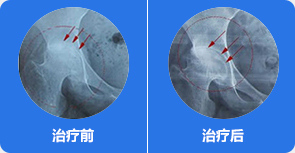

治疗前:通过影像,可知道股骨头周边血管分布、病灶部位,血管哪里堵塞清晰可见

治疗中:旋股内侧动脉中的血脂、血栓逐渐被疏通

治疗后:通过融通术,旋股内侧动脉逐渐恢复血供,骨关节周围血流量加快,骨细胞供血恢复正常